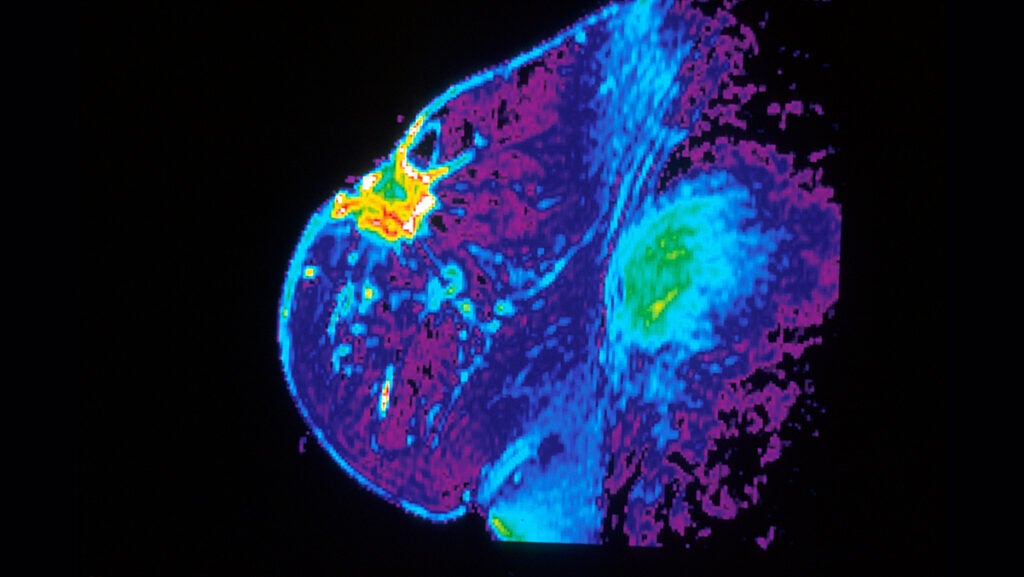

MRI May Lower Breast Cancer Deaths From Variants in Three Genes